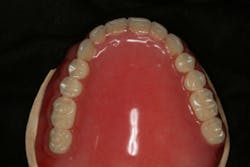

In this case, the diagnostic wax-up of the mounted models gave the technician the new position of the upper incisal edge. The technician then set the maxillary teeth appropriately using models and additional photographs. At the same time, tooth No. 20 was restored, but the lab technician kept the crown and lower partial to predictably create the lower occlusal plane and easily articulate this with the upper immediate denture (figure 18). Note the improved curve of Spee in Figures 19 and 20. Upon completion of the prosthesis, treatment was completed as outlined and the results made the patient feel very comfortable functionally, esthetically, and phonetically.

There was some fine-tuning to the patient's occlusion during the healing period. Nevertheless, the goals of treatment were accomplished very predictably. Figures 21 (horizontal position) and 22 (vertical position) verify both the new vertical and horizontal positions of the upper incisal edge.

Understanding the patient’s masticatory system requires the dentist to gather the correct data through a comprehensive examination. (6) In addition, diagnostic records (mounted models in centric relation and digital photography) can be used to provide predictable results. The overall esthetic outcome, along with improved function, gave the patient a new outlook on life and increased confidence—all within her budget (figures 23–25). The Dawson Academy is a great resource for learning about the masticatory system, functional esthetics, and a predictable treatment-planning protocol.